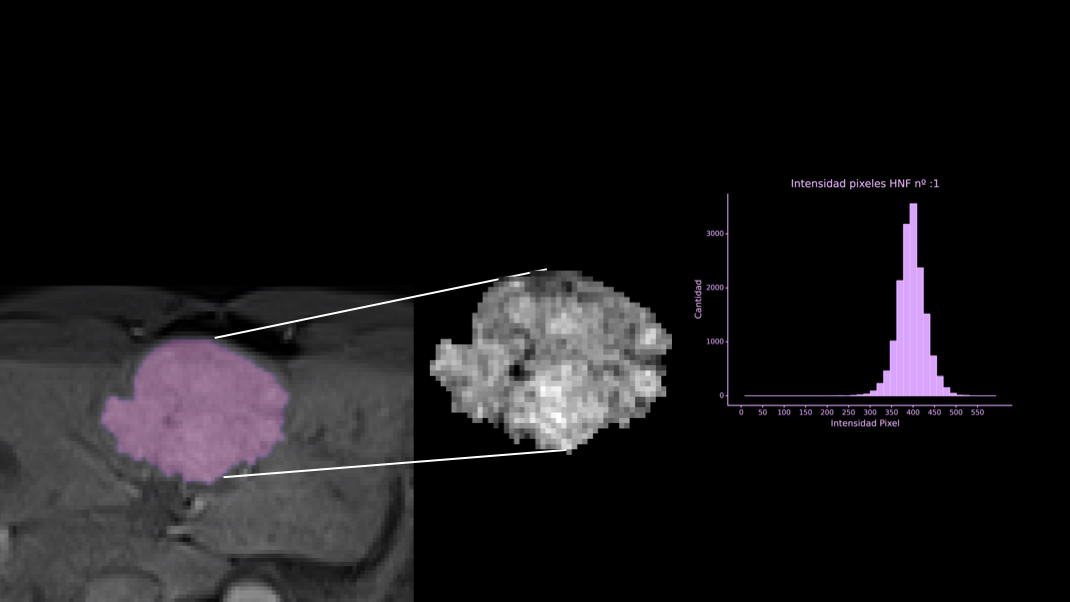

Aprende los fundamentos teóricos de radiómica en Medicina de Precisión y aplica los conocimientos aprendidos en nuestros talleres prácticos con datos reales en los que aprenderás desde cero a implementar proyectos de Radiomics utilizando Python y herramientas de segmentación y modelado 3D.